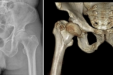

车祸患者严重骨折,茂医骨科机器人“巧手”辅助微创修复

市民不慎高空坠落致严重骨折,茂医骨科机器人助力修复